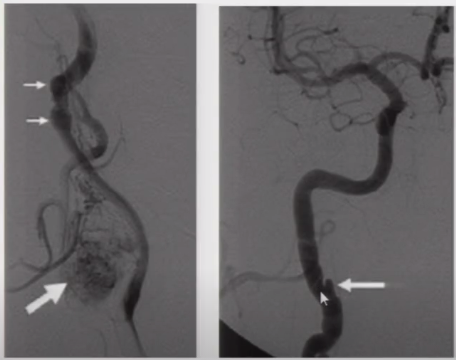

3. 颈动脉蹼(Carotid artery web)

➤ 动脉腔内隔膜状突出物(有时班瘤样扩张),多出现在颈动脉球部,为非典型的内膜下棘状细胞纤维增生物,不伴内皮的增生,无炎性细胞浸润,无脂质浸润;

➤ 多发生在颈动脉(颈动脉球附近),也可见于椎动脉;

➤ 引起血管狭窄;在蹼的远心面形成血流的滞留区,从而产生血栓;

➤ CTA上可见血管腔内充盈缺损,DSA上尚可见到造影剂滞留。

图3 颈动脉蹼

➤ 颈动脉蹼

图10